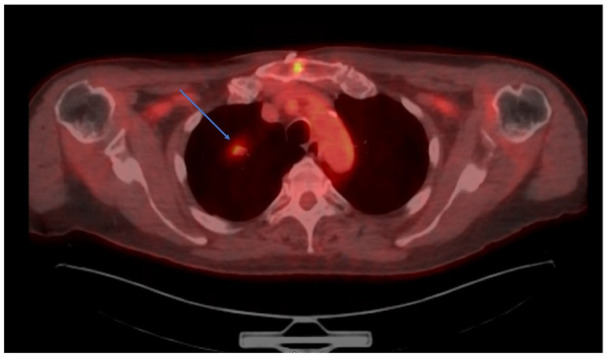

支气管相关淋巴组织(BALT)淋巴瘤是结外边缘区b细胞淋巴瘤的一种罕见亚型,占不到5%的病例。它通常是惰性的,通常是由于不相关的原因通过影像学检查偶然发现的。我们提出的情况下,一个72岁的男性胸主动脉扩张史已知,谁被发现有一个针状右上叶(RUL)肺结节的监测成像。他仍然无症状,没有体质或呼吸道症状。正电子发射断层成像显示RUL结节摄取轻度增加(标准化摄取值2.4),未见纵隔或肝门淋巴结病变。支气管镜活检,组织病理学和免疫组织化学显示低级别b细胞非霍奇金淋巴瘤,CD20和BCL2阳性。流式细胞术证实单克隆b细胞增生,荧光原位杂交分析证实BIRC3-MALT1易位,与BALT淋巴瘤一致。患者分期为IE,考虑到其疾病的局限性和无症状性,决定采取保守治疗和主动监测。虽然治疗方案可能包括手术、放疗、免疫治疗或化疗,但由于这种淋巴瘤的罕见性和异质性,对最佳方法尚无共识。在许多没有症状的早期病例中,“观察和等待”策略是合理的。该病例强调了将BALT淋巴瘤纳入偶发性肺结节鉴别诊断的重要性,并强调了提高认识和研究以建立标准化治疗方案的必要性,每个病例都为指导未来的管理策略提供了有价值的见解。

Bronchus-associated lymphoid tissue (BALT) lymphoma is a rare subtype of extra-nodal marginal zone B-cell lymphomas, accounting for less than 5% of cases. It is typically indolent and often discovered incidentally through imaging studies performed for unrelated reasons. We present the case of a 72-year-old male with a known history of thoracic aortic dilatation, who was found to have a spiculated right upper lobe (RUL) pulmonary nodule on surveillance imaging. He remained asymptomatic, with no constitutional or respiratory symptoms. Positron emission tomography imaging demonstrated mildly increased uptake (standardized uptake value 2.4) of the RUL nodule, and no mediastinal or hilar lymphadenopathy. Bronchoscopic biopsy with histopathology and immunohistochemistry revealed a low-grade B-cell non-Hodgkin's lymphoma, with CD20 and BCL2 positivity. Flow cytometry confirmed monoclonal B-cell proliferation, and fluorescence in situ hybridization analysis identified the BIRC3-MALT1 translocation, consistent with BALT lymphoma. The patient was staged as IE, and a decision was made for conservative management with active surveillance, given the localized and asymptomatic nature of his disease. While treatment options may include surgery, radiotherapy, immunotherapy, or chemotherapy, there is no consensus on the optimal approach due to the rarity and heterogeneous presentation of this lymphoma. In many early-stage cases without symptoms, a "watch and wait" strategy is reasonable. This case underscores the importance of including BALT lymphoma in the differential diagnosis of incidental pulmonary nodules and highlights the need for greater awareness and research to establish standardized treatment protocols, with each case adding valuable insight to guide future management strategies.